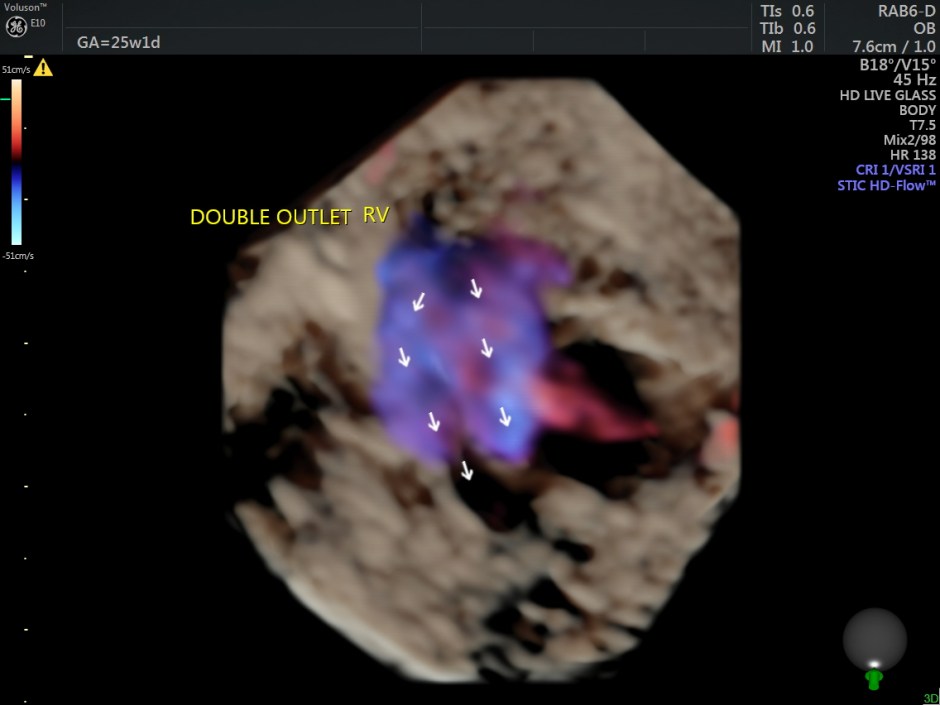

The following are some reconstructions.

This fetus showed left heart dysplasia, a small VSD and Double Outlet Right Ventricle with malposition of the great arteries.